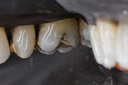

Joe Cha #29 pre-op

Joe Cha #29 prep